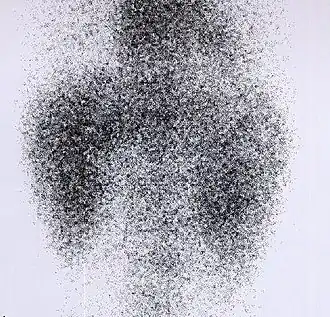

DMSA scan

Decreased Tc99m-DMSA uptake in both kidneys, suggestive of renal failure. | |